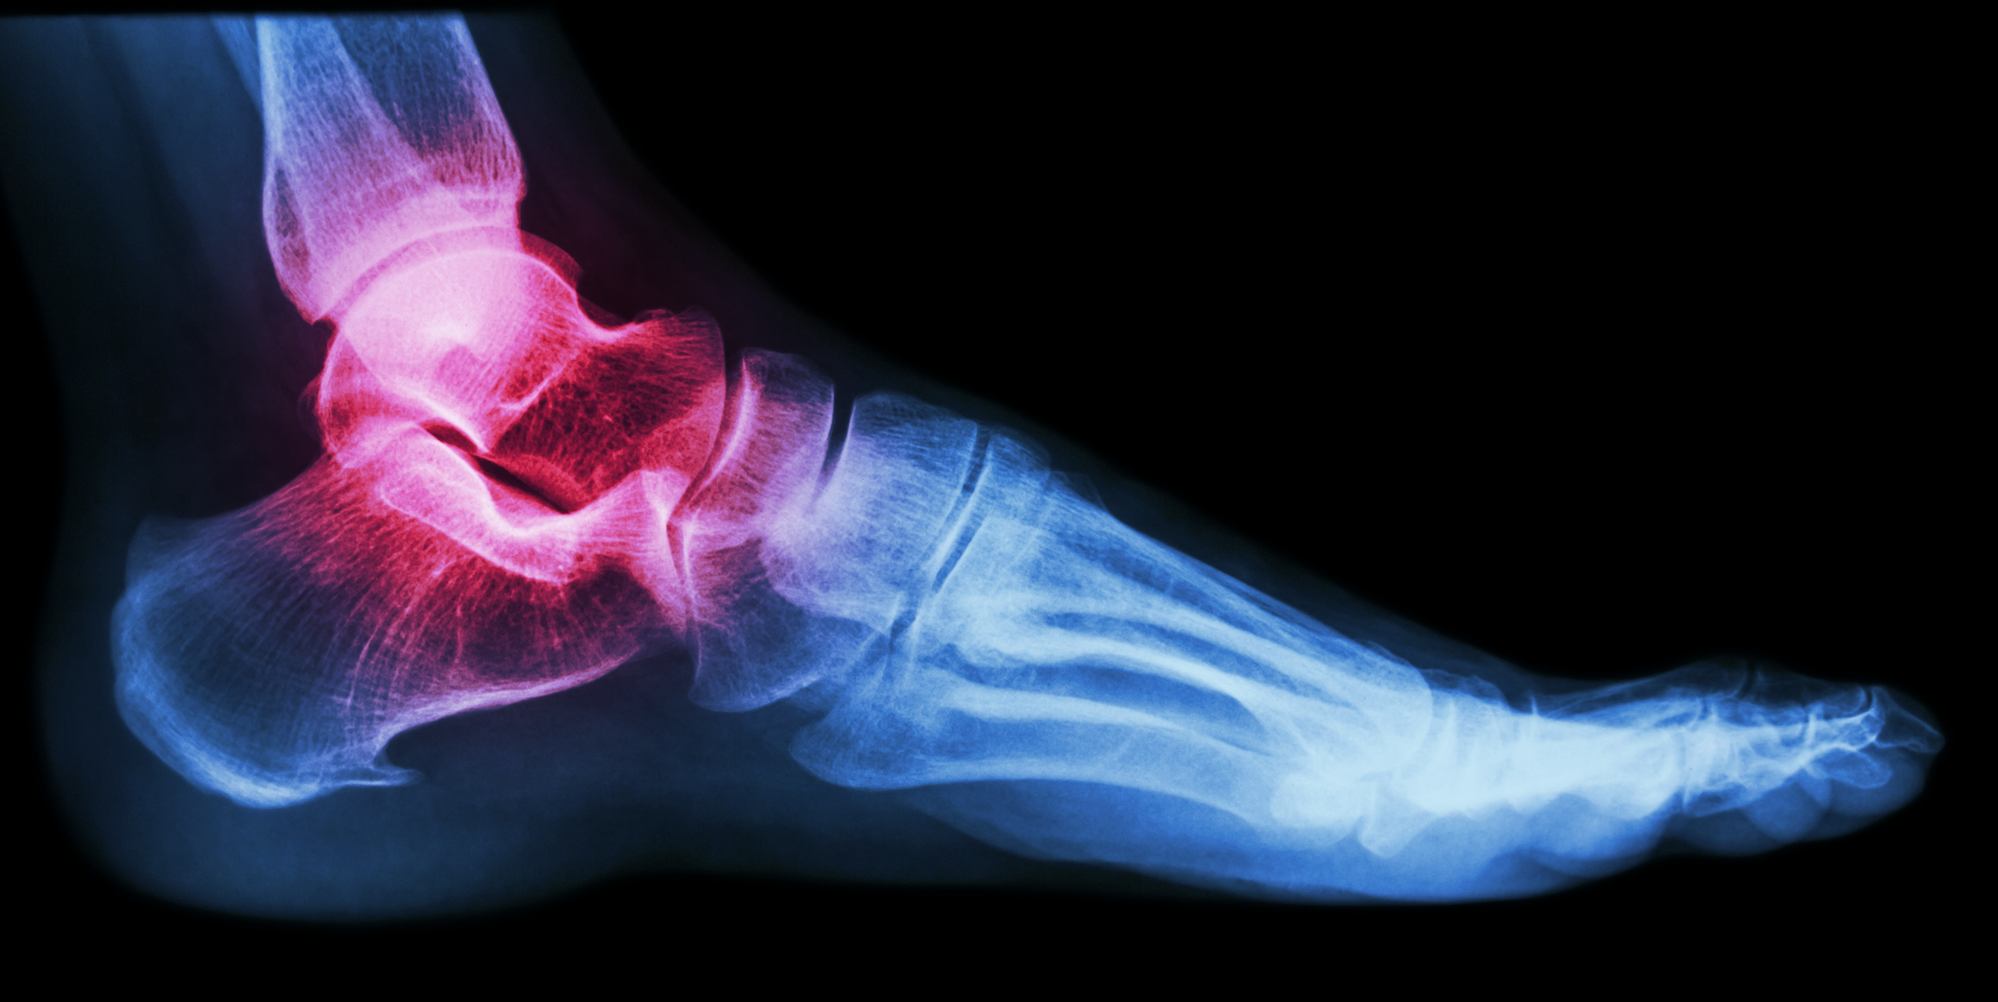

When your feet are misaligned, it leads to a chain reaction of misalignment in the body, affecting the knees, hips and back, often resulting in pain when standing, walking and running. The most common sign of misaligned feet is the inward rolling of the ankles, which is called Hyperpronation. However, misaligned feet can lead to a variety of other symptoms including, flat feet, foot pain, back pain, knee pain, hip pain, bunions and hammertoe.

HyProCure corrects irregular foot form and alignment. The procedure uses an incision in your arch to correct the misaligned bones in your foot, allowing your bones to move freely again. HyProCure also reduces pressure on nerves, which can cause pain and inflammation.